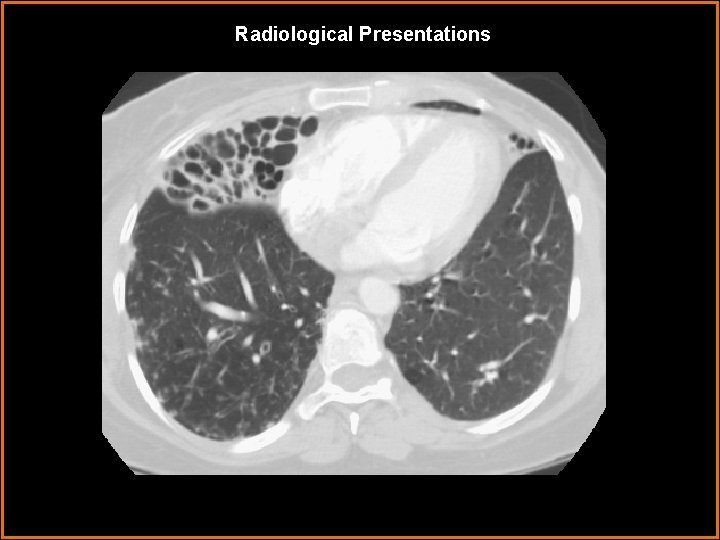

Radiological Presentations

Findings and Differentials Findings: There is extensive bronchiectasis in the right middle lobe. Bronchiectasis is also seen in the lingula. Small alveolar opacities are arranged in a tree-in-bud distribution in portions of the right lower lobe. Differentials: • Mycobacterium avium complex (MAC) pneumonia • Chronic bacterial pneumonia